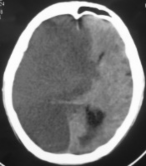

Hình 3.3. Tổn thương toàn bộ bán cầu sau tắc động mạch cảnh trong